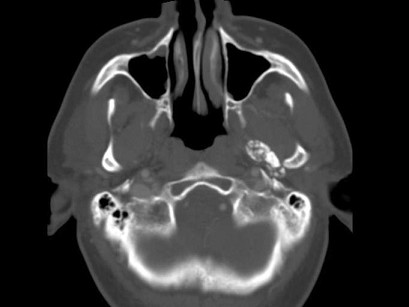

男,60岁,张口受限半年,CT检查如图所示,正确的描述或诊断是()

A.左侧颞颌关节周围软组织内见较多致密钙化影

B.左侧颞颌关节软组织未见肿胀

C.左侧颞颌关节面(颞骨面)骨质增生明显

D.左侧颞颌关节滑膜骨软骨瘤病

E.颞颌关节功能紊乱